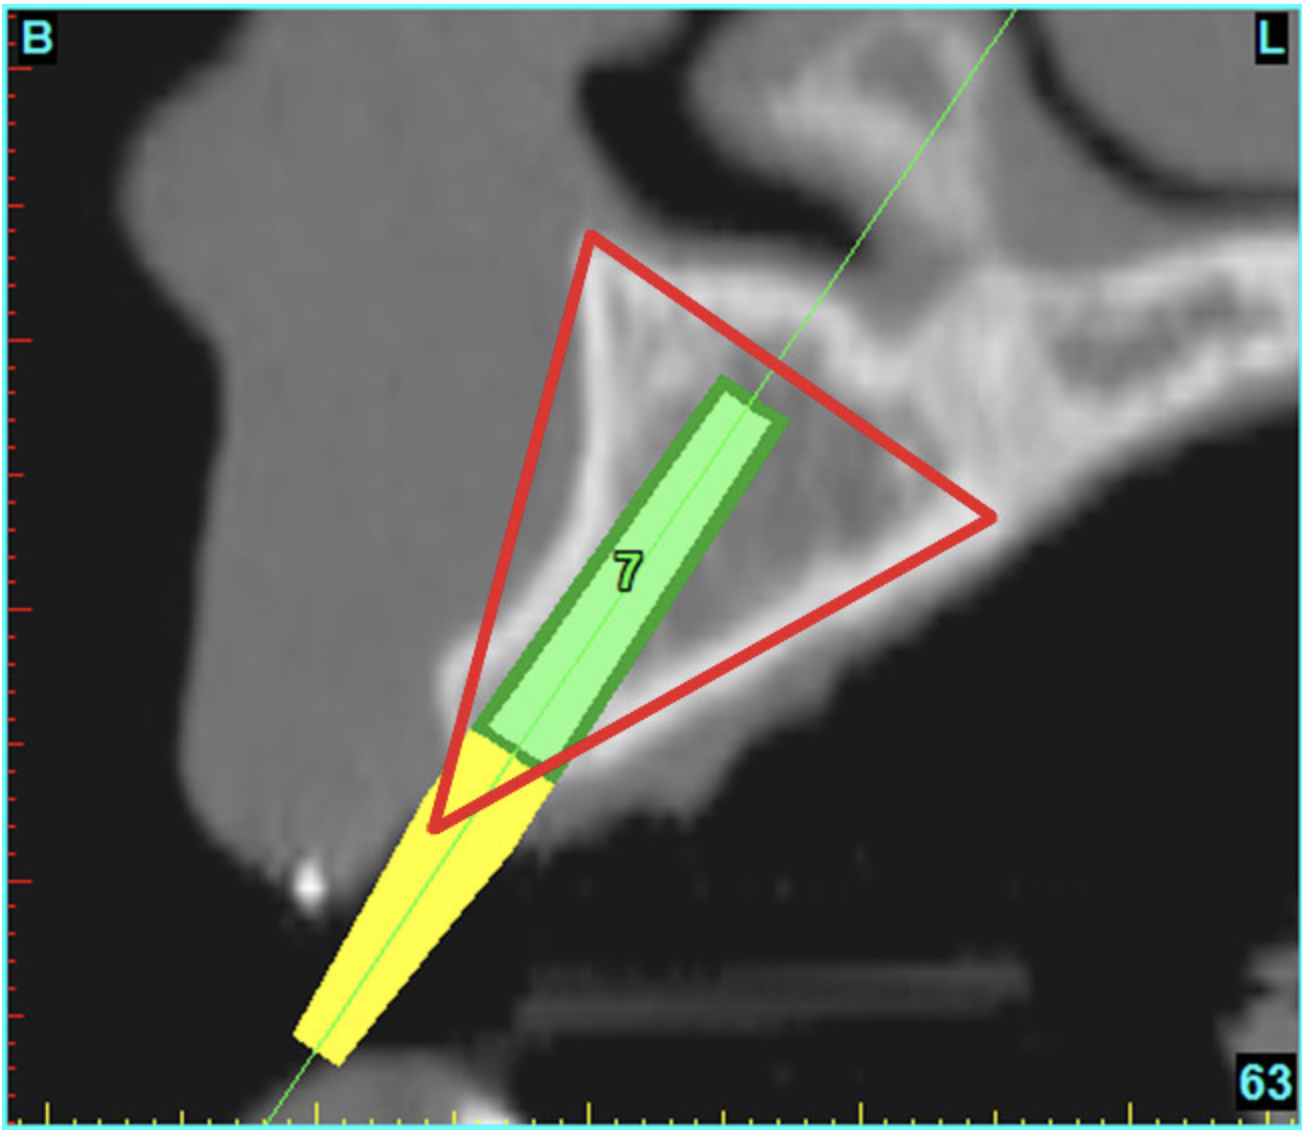

Using the interactive treatment-planning software application, the scan data was assimilated and both potential lateral incisor implant receptor sites were evaluated. It is a combination of the data and the methodology used to interpret the data that is the basis for defining a new paradigm in diagnosis and treatment planning. Proper evaluation of these images and correct use of the interactive treatment-planning software tools is essential in creating a decision tree of treatment options. First, the data from the scan was reformatted into panoramic, axial, and cross-sectional images. The undistorted cross-sectional images revealed the residual alveolar bone in the area of the right lateral incisor. Then, a simulated schematic implant was placed within the bone with an abutment extension to help visualize the connection to the restorative position of the tooth (Figure 4A). The Triangle of Bone® (TOB), a concept developed by the author to analyze bone quality, quantity, and disposition at prospective dental implant sites using CBCT scans, aided in determining available bone volume by defining a “zone” for proper implant placement18,19 (Figure 4B).

After reviewing the CT data and the decision tree, the bone within the “zone” of the TOB was evaluated and found to be satisfactory for implant placement. Because the goal of implant dentistry is not the implant but the tooth that is placed, true restorative-driven implant dentistry must begin with the assumption that the implant position should remain consistent with the tooth it is replacing, and the final implant-supported restoration.12,22-26 The TOB aids the clinician in understanding the link between the implant position and the desired restorative goal. The base of the geometric shaped “zone” is visualized by starting at the widest area of alveolar bone facially and superiorly. The apex of the triangle is positioned to bisect the alveolar crest (Figure 4B). The TOB, the overlay in the cross-sectional image, reveals whether adequate bone is available for implant placement. It also helps to identify concave facial bone defects, and accurately determine the width of bone at the crest. The author recommends using an interactive software application that provides the necessary measurement tools to accurately assess the bone anatomy.

Figure 7a  The 3D reconstruction showed (A) the facial concavities and root eminences, and allowed (B) for evaluation of virtual implant placement to ensure the facial cortical plate was not perforated.

Figure 7a

Figure 7b  The 3D reconstruction showed (A) the facial concavities and root eminences, and allowed (B) for evaluation of virtual implant placement to ensure the facial cortical plate was not perforated.

Figure 7b